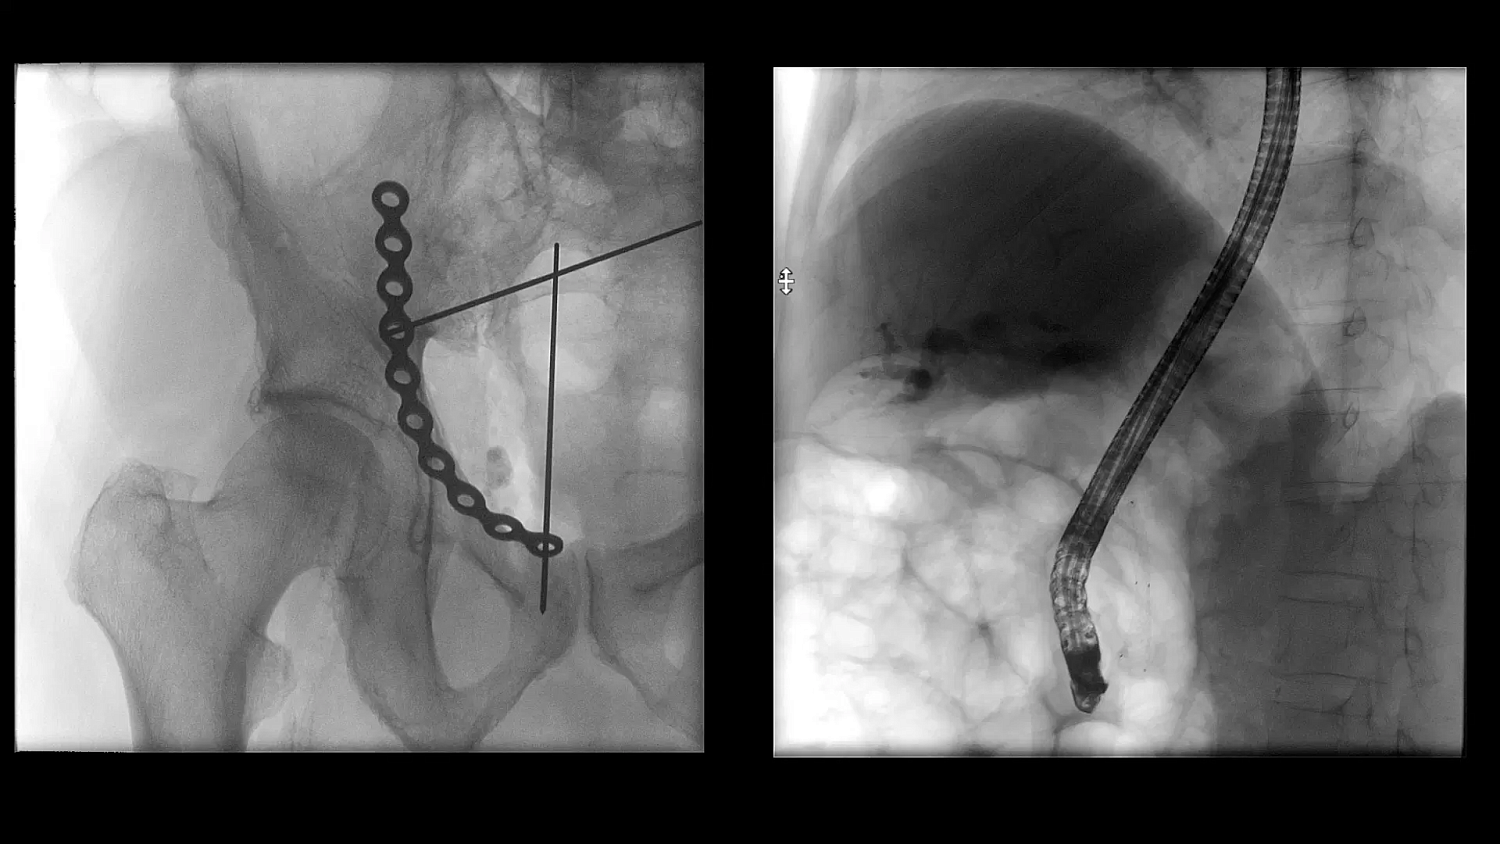

- Улучшенная цепочка визуализации матричного детектора с технологией CMOS: интеллектуальные алгоритмы автоматически регулируют яркость и контрастность, обнаруживают движение, улучшают края и оптимизируют визуализацию металла для улучшения изображения окружающих тканей

- SpotAdapt и сенсорные жесты: SpotAdapt автоматически оптимизирует параметры визуализации в соответствии с интересующей анатомией. Сенсорные жесты, как на планшете, позволяют коллимировать, поворачивать и переворачивать изображения, а также использовать преимущества SpotAdapt всего одним пальцем.

Больницы сталкиваются с ростом стоимости медицинского оборудования, поэтому им необходимо оправдать инвестиции. Cios Flow — это многофункциональная система, которую можно использовать в различных областях — ортопедической и травматологической хирургии, хирургии позвоночника, сосудистой хирургии и т. д. — позволяя повысить эффективность использования своих ресурсов.